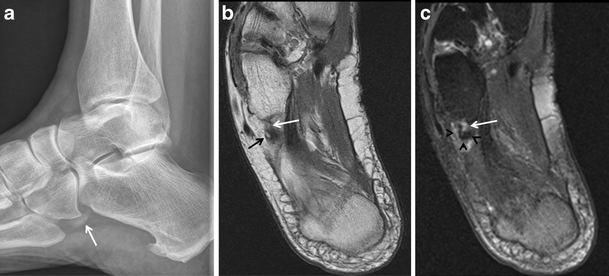

Painful os peroneum syndrome. a Lateral radiograph of the ankle demonstrates the presence of an os peroneum (white arrow). Axial proton density-weighted (b) and T2-weighted fat-saturated (c) MRIs of the ankle show focal tendinosis at the peroneus longus tendon (white arrows) just distal to the os peroneum (black arrow) and surrounding soft tissue oedema (arrowheads). These findings corroborate a painful os peroneum syndrome